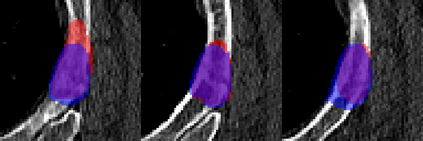

Rib fractures are a common and potentially severe injury that can be challenging and labor-intensive to detect in CT scans. While there have been efforts to address this field, the lack of large-scale annotated datasets and evaluation benchmarks has hindered the development and validation of deep learning algorithms. To address this issue, the RibFrac Challenge was introduced, providing a benchmark dataset of over 5,000 rib fractures from 660 CT scans, with voxel-level instance mask annotations and diagnosis labels for four clinical categories (buckle, nondisplaced, displaced, or segmental). The challenge includes two tracks: a detection (instance segmentation) track evaluated by an FROC-style metric and a classification track evaluated by an F1-style metric. During the MICCAI 2020 challenge period, 243 results were evaluated, and seven teams were invited to participate in the challenge summary. The analysis revealed that several top rib fracture detection solutions achieved performance comparable or even better than human experts. Nevertheless, the current rib fracture classification solutions are hardly clinically applicable, which can be an interesting area in the future. As an active benchmark and research resource, the data and online evaluation of the RibFrac Challenge are available at the challenge website. As an independent contribution, we have also extended our previous internal baseline by incorporating recent advancements in large-scale pretrained networks and point-based rib segmentation techniques. The resulting FracNet+ demonstrates competitive performance in rib fracture detection, which lays a foundation for further research and development in AI-assisted rib fracture detection and diagnosis.